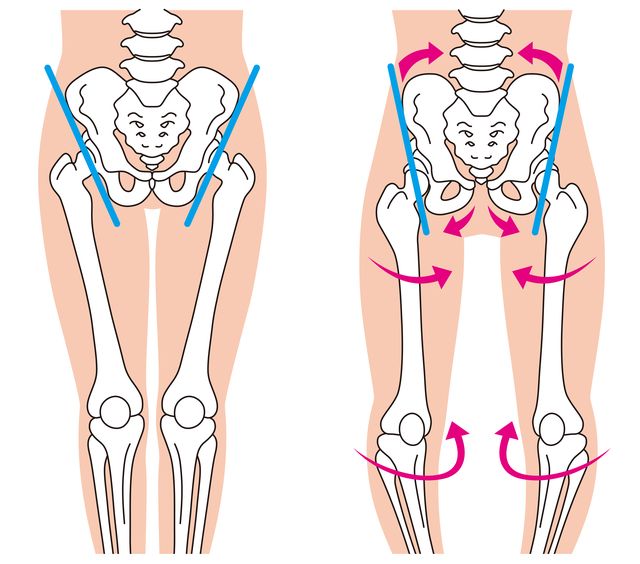

股関節の状態の変化

股関節の変形

股関節の痛みは、関節の状態に変化が生じることで起こる場合があります。その背景には、さまざまな要因が関係していると考えられています。

・股関節に負担のかかるスポーツや動作を続けている

・長期間にわたる立ち仕事や重い物を扱う作業

・体重増加による関節への負担

・生まれつきの股関節の形状の特徴

また、姿勢のくせや筋肉の疲労、生活習慣、体の使い方などが影響して痛みが出ることもあります。原因は一つとは限らず、複数の要因が重なっている場合も少なくありません。